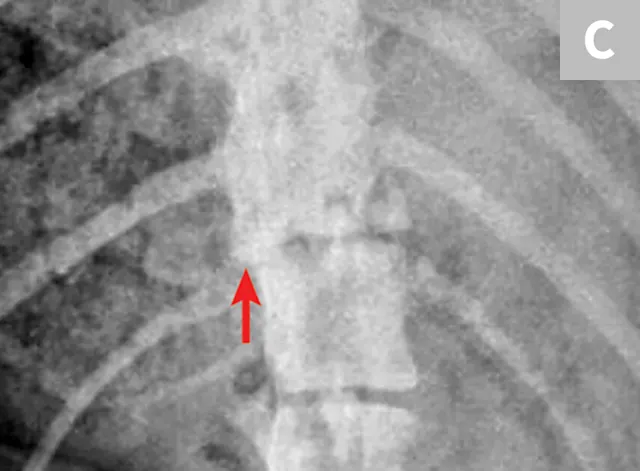

Figure 1

Lateral radiograph of a dog following unknown trauma. There is a complete oblique fracture (arrow) of the L6 vertebral body and luxation of the L6-L7 articular processes, with severe cranioventral displacement of the caudal segment. Despite the degree of displacement, this patient retained voluntary movement in both pelvic limbs on initial examination and made a functional recovery following reduction and stabilization of the fracture/luxation and 8 weeks of crate confinement.